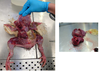

Ætologi: Salmonella Pullorum. På billede ses oophoritis

Salmonella Pullorum / Histomonas(blackhead).

Billede af Cecum

Salmonella Pullorum

Nekrose i myocardium, lyse områder

Salmonella Pullorum

Salmonella Pullorum

Salmonella Pullorum

Organ forstørrelse

Salmonella Pullorum